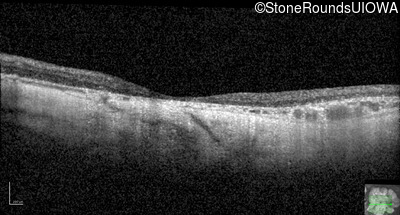

Visit at age: 76 years

Optical Coherence Tomography - Right - 20/150

Exemplar / OCT Stack